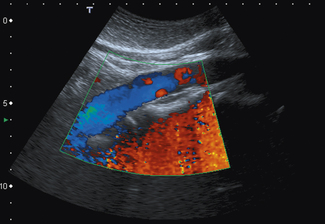

It is probably the first Doppler technique that an operator will utilize to investigate blood flow. Color flow imaging is always used in conjunction with B-mode imaging and once it is activated the operator is presented with a region of interest known as the ‘color box’ and vertical ‘color scale’ bar which are superimposed onto the B-mode image, as illustrated in Figure 11.8.

image

Fig. 11.8 B-mode image with color flow information superimposed. Note that color flow information is only mapped into the color box region. Vertical color scale bar present on the right-hand side of the display

The position and size of this color box can be adjusted to the chosen area of interest by the operator to provide a visual color-coded display or map of blood flow.

For each individual sample volume along each scan line, the average or mean Doppler shifted velocity is calculated. This mean Doppler shifted velocity, which can either be positive or negative, is assigned a color which is then mapped onto a color scale which consists of two primary colors. This is usually red for positive Doppler shifted signals (corresponding to blood flow traveling towards the transducer) and blue for negative Doppler shifted signals (corresponding to blood flow away from the transducer). This typical arrangement can be seen in Figure 11.8.

The color scale is represented as a vertical color bar and normally sits to the side of the B-mode image (see Fig. 11.8). Closer inspection of the color bar shows that it consists of two primary colors with each primary color subdivided into different shades or hues.

Figure 11.10 illustrates a typical color scale bar used. As you can see, it consists of a vertical color bar which is split from the center into two primary colors. The center of a standard color bar scale represents zero or no flow. In this case, blood flow towards the transducer will be labeled red and blood flow away from the transducer is labeled blue. However, in most equipment this color bar scale can be changed, if required, by the operator.

Fig. 11.10 Typical color scale bar. Blood flowing towards the transducer is displayed as RED, blood flowing away from the transducer is BLUE. The brighter shades indicate higher velocities